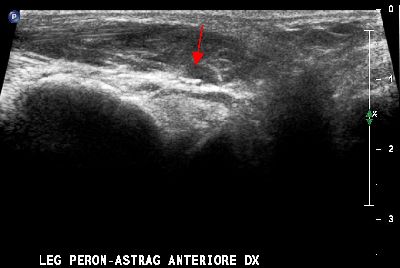

Lesione legamento peroneo-astragalico anteriore Lesione legamento peroneo-astragalico anteriore